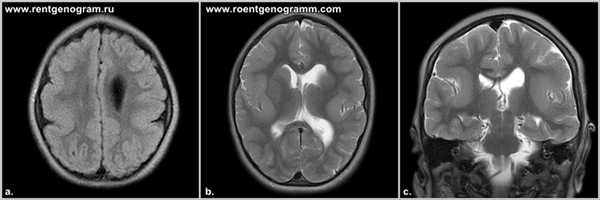

Агенезия возникает при нарушении дифференциации нервной трубки в период со 2 до 5 месяца внутриутробного развития. При полном отсутствии МТ третий мозговой желудочек остается открытым, не формируются столбы свода мозга, отсутствуют прозрачные перегородки. В 60% случаев при АМТ передней комиссуры нет вообще. В 10% она увеличена и берет на себя часть функций мозолистого тела у новорожденных, а также на следующих этапах постнатального периода.

Характерным анатомическим изменением является колпоцефалия, при которой расширены задние отделы боковых церебральных желудочков. Состояние не относится к истинной гидроцефалии новорожденных, а обусловлено уменьшением кортикальных ассоциативных путей. Еще один типичный признак порока — пучки Пробста, представляющие собой неправильно ориентированные аксоны, расположенные параллельно межполушарной щели.

- КТ головного мозга. При компьютерной томографии определяются широко расставленные передние рога, высокое стояние третьего желудочка, параллельный ход медиальных стенок боковых желудочков. КТ производится в рамках постнатальной диагностики.

- МРТ головного мозга. Для максимально точной визуализации степени агенезии или гипоплазии мозолистого тела новорожденным выполняется магнитно-резонансная томография в трех плоскостях. По показаниям МРТ может рекомендоваться беременным женщинам для исключения несовместимых с жизнью сочетанных пороков ЦНС.